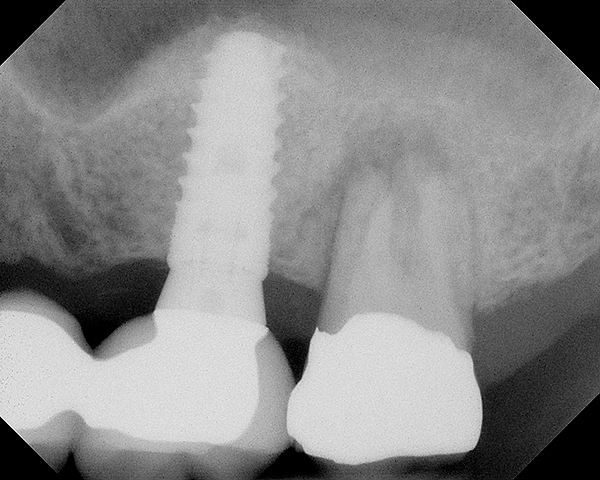

Fig 16. 4-month radiograph with the abutment No. 14 in place. Note the ill-defined old sinus floor.

figure 16

A 74-year-old man presented with only about 2 mm to 3 mm of native bone below the sinus in the No. 14 position (Figure 13). The composite graft used was an approximately 50:50 mixture of DFDBA (Bio-Oss®, Geistlich Biomaterials, www.bio-oss.com) with the addition of about 40% calcium sulfate by volume (Figure 14). The implant placed (Figure 15) was a 10-mm long, rough-surfaced, platform-shifting implant (tapered 4.2 mm to 2.8 mm), and the sinus was raised about 8 mm. The postoperative radiograph taken at 4 months (Figure 16) showed some shrinkage of the graft, but no demarcation of the old sinus floor in the area.